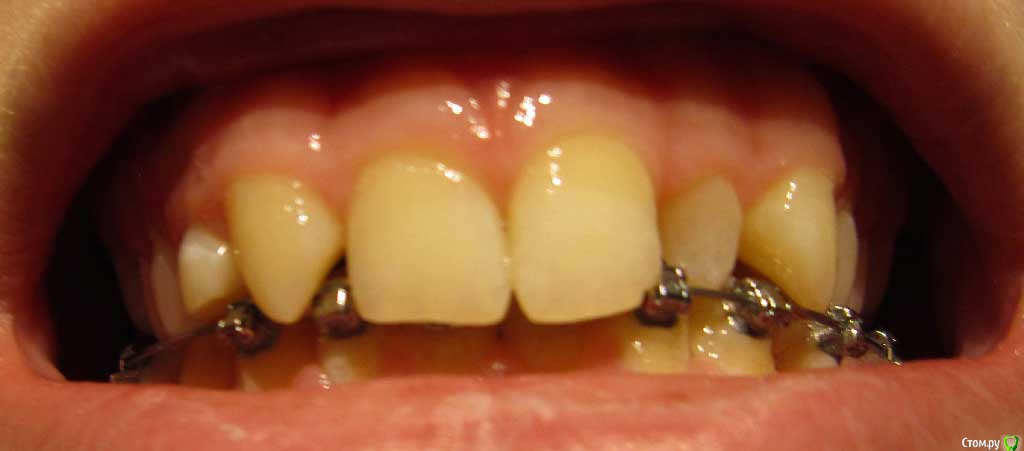

Сейчас мне 17 лет. На лечении у ортодонта с августа 2013 года. Удалили молочные пятерки и стали сдвигать шестерки к передним зубам. На верхнюю челюсть она ставить брекеты не стала. Осенью 14 года врач ушла в декрет.

Пришел новый врач который предложил все сделать несколько иначе: поставить брекеты на обе челюсти, все выравнять и освободить место под будущие импланты: вместо пятерок снизу и второго слева резца сверху -, а пока на их место поставить коронки. Также врач назвал сроки: около 1 года.

Сверху слева отсутствует зачаток второго резца, вместо него находится клык и молочный зуб левее. Внизу нет зачатков пятерок.